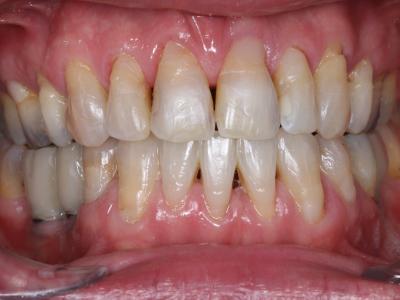

Sur le plan parodontal, le contrôle de plaque insuffisant et l’accumulation importante de tartre sur l’ensemble des dents maxillaires et mandibulaires entraînent une gingivite étendue. Des récessions importantes sont également visibles. Les sondages ne relèvent quant à eux aucune poche parodontale ni perte osseuse notable. La formule dentaire indique l’absence de 36, 45, 46, non remplacées, l’absence de 15, 25, 31, avulsées étant plus jeune pour créer de la place en vue du traitement orthodontique et celle de 28, 38 étant sans antagoniste.

Une classe 1 d’angle, une hyperdivergence faciale et une endognathie maxillaire sont diagnostiquées grâce à l’analyse céphalométrique. Sur le plan alvéolaire, une classe 2 molaire, une classe 3 canine (par la perte de 31), une infraclusie incisive ainsi qu’un encombrement maxillaire et mandibulaire sont à observer. Certains soins méritent d’être repris par perte d’étanchéité. En outre, pour des raisons purement esthétiques, le patient désire remplacer tous ses amalgames dentaires.

Pour parvenir à niveler les arcades sans augmenter l’infraclusie incisive par égression des dents des secteurs postérieurs, des implants ont été placés en 36, 35, 46 avant le début du traitement orthodontique. Surmontés de couronnes provisoires transvissées, en sous occlusion, les implants ont servi d’ancrage à l’ingression des molaires mandibulaires. Dans le même temps, des mini-vis d’ancrage sont placées à l’arcade maxillaire pour favoriser à la fois l’ingression des molaires et supprimer l’endoalvéolie. Enfin, un appareil multi-attaches a permis la parallélisassions des axes dentaires, l’alignement des dents et la congruence des arcades.